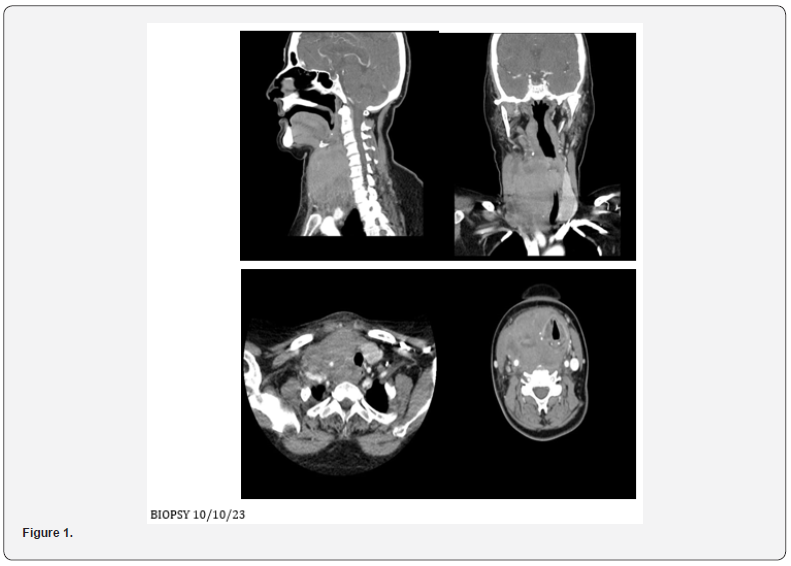

Ct Neck Contrast 4/10/23

• Large solid enhancing lesion is identified arising from

the right lobe of thyroid gland, which is completely replaced by

the lesion and is extending into the isthmus. Few necrotic areas

identified within the lesion along with few specks of calcification.

The lesion measures approximately 57 x 72 x 95 mm.

• Minimal retrosternal extension identified.

Anteriorly the lesions infiltrating the strap muscles and right

sternocleidomastoid muscle. Posteriorly it involves prevertebral

fascia. Laterally it is encasing the trachea and displacing it

towards the left side however, no significant tracheal narrowing

is noted. Bilateral thyroid cartilage is also involved in the lesion. It

is also compressing and displacing the esophagus towards the left

side. The lesion is also encasing the right common carotid artery.

Superiorly it is reaching up to the level of hyoid bone. The right

piriform fossa and vallecula are effaced due to mass effect. The

posterior wall of the hypopharynx appears to be infiltrated by

the lesion. The right brachiocephalic vein is also encased by the

lesion. The internal jugular vein is significantly attenuated.

• Few enlarged cervical lymph nodes are noted, largest

one is noted in right level IIb, measuring approximately 13 mm

in short axis. Left lobe of thyroid gland appears normal and is

significantly displaced towards the left side. Significant fat atrophy

of bilateral submandibular glands is noted. Mild fatty replacement

is also noted in bilateral parotid glands. Tongue and floor of mouth

appear normal. Nasopharynx appears normal. Epiglottis and

fossae of Rosen Mueller appear normal. Paranasal sinuses and

mastoid air cells appear clear (Figure 1).